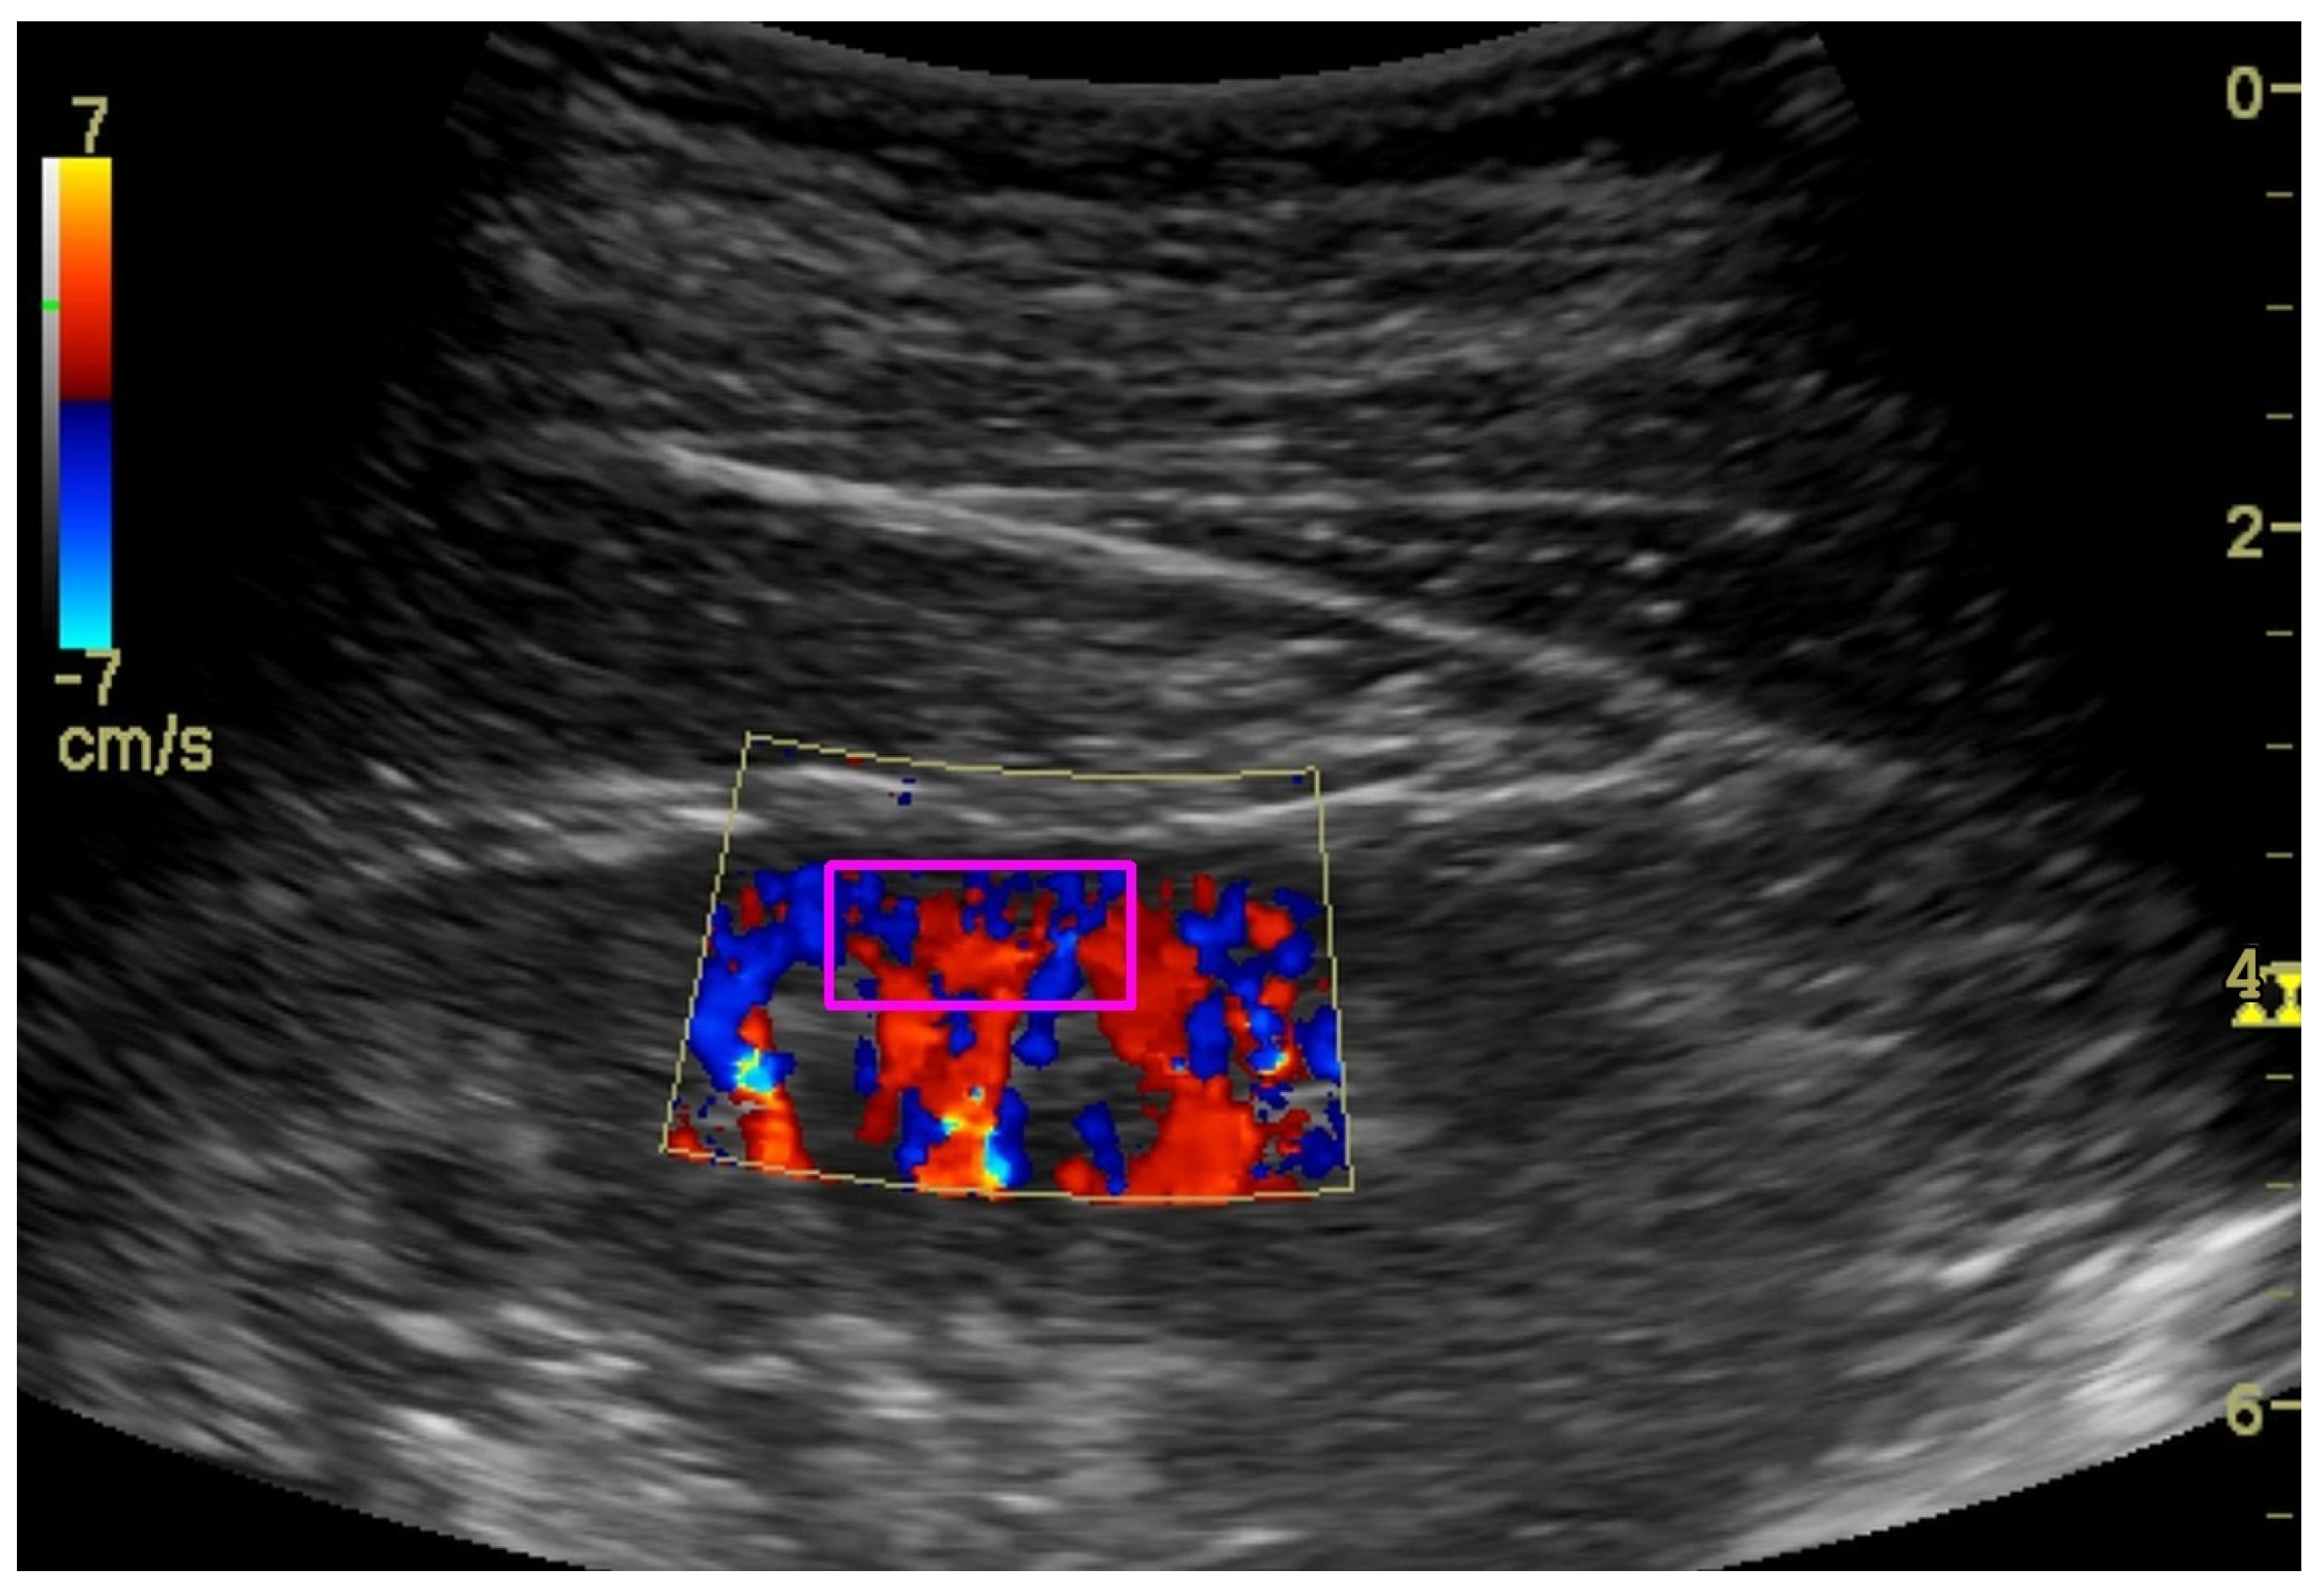

| dRCP (cm/s) | 0.483 | 0.452 | 0.303 | 0.529 |